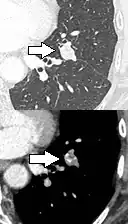

If there is an intermediate risk of malignancy, further imaging with positron emission tomography (PET scan) is appropriate (if available). It can be done simultaneously as a CT scan in the form of PET-CT. Around 95% of patients with a malignant nodule will have an abnormal PET scan, while around 78% of patients with a benign nodule will look normal on PET (this is the test sensitivity and specificity).[15] Thus, an abnormal PET scan will reliably pick up cancer, but several other types of nodules (inflammatory or infectious, for example) will also show up on a PET scan. If the nodule has a diameter of less than one centimeter, PET scans are often avoided because of an increased risk of falsely normal results.[15][16][17] Cancerous lesions usually have a high metabolism on PET, as demonstrated by their high uptake of FDG (a radioactive sugar).

-

PET-CT of a tuberculoma.